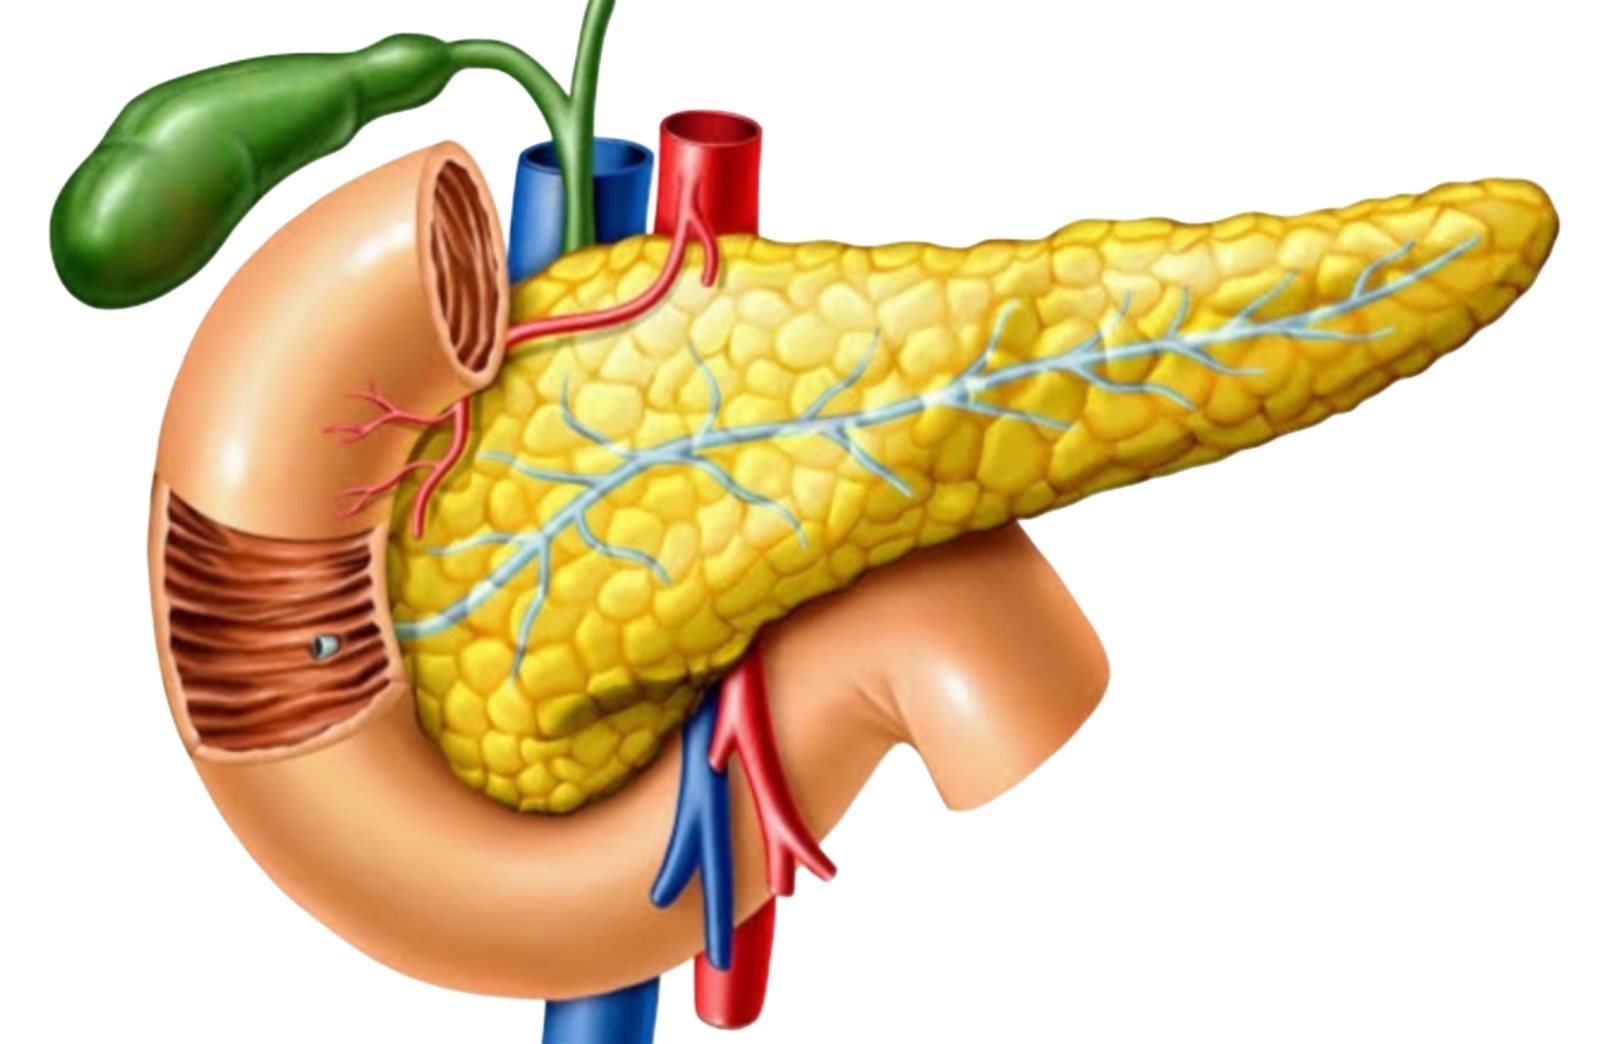

جزر البنكرياس

إن الجزر الموجودة في البنكرياس عبارة عن مجموعات من الخلايا المفرزة للأنسولين وخلايا أخرى متشابكة في أوعية دموية صغيرة متخصصة.

في الواقع، إن خلايا بطانة الأوعية الدموية الرخوة المشتقة من خلايا الوريد السري البشري متينة نسبيًا في ظروف زرع الأعضاء، على عكس الخلايا البطانية الهشة الموجودة في جزر لانجرهانس، وهي مصممة لتكون قابلة للتكيف بدرجة كبيرة، وتدعم أي نوع محدد من الأنسجة يحيط بها.